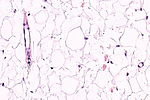

- The layer below the skin is the subdermis (AKA hypodermis, AKA subcutaneous tissue).

- It is below the dermis and consists of adipose tissue.[3]